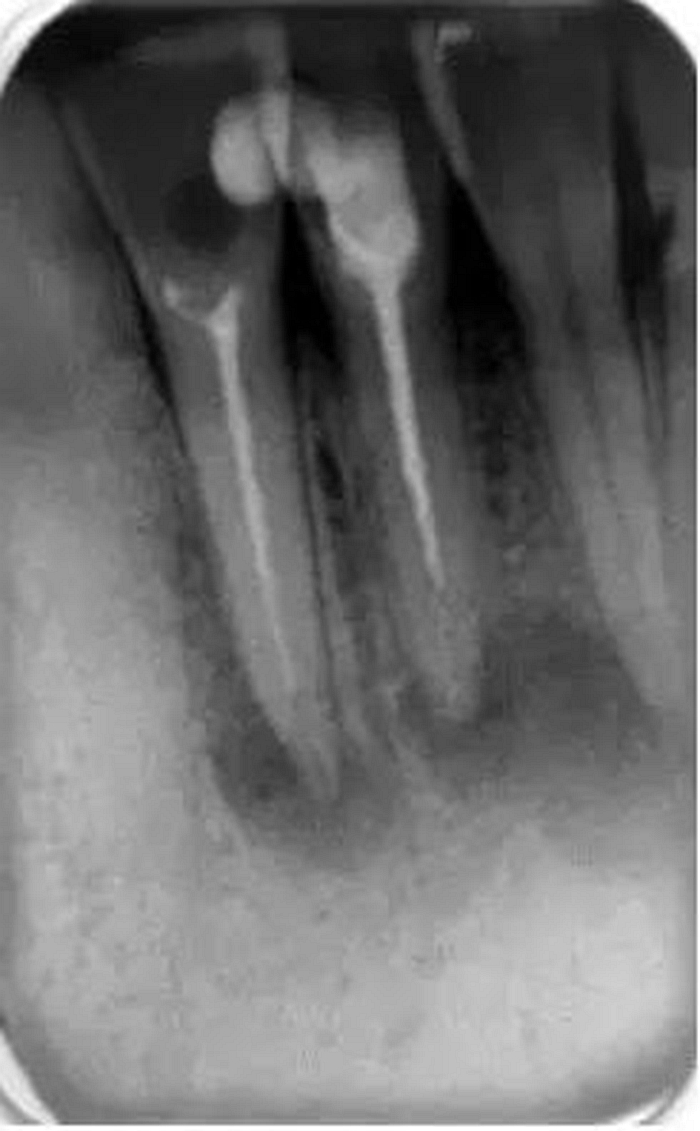

它還有助于臨床醫(yī)生決定他是否有能力進(jìn)行該病例的治療還是應(yīng)該將患者轉(zhuǎn)診到??漆t(yī)生處進(jìn)行治療。還可以在治療前明確髓腔內(nèi)是否有髓石以及牙齒或根管內(nèi)是否有其他阻塞物(如樁、釘、分離的儀器或根填充材料)(圖2)。這是很重要的,因?yàn)樗鼤o臨床醫(yī)生一些預(yù)后和治療中可能出現(xiàn)的一些問題的提示。所有這些因素必須在治療前與患者進(jìn)行溝通,以便其決定是否要繼續(xù)進(jìn)行根管治療。